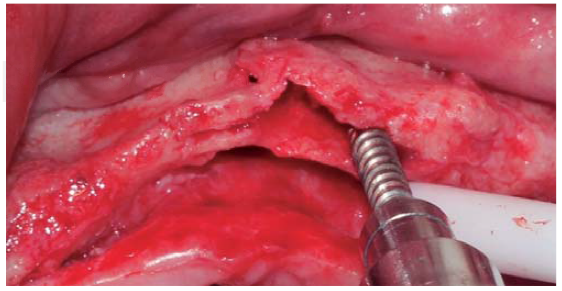

A full thickness incision over the crest was performed, raising a mucoperiosteal flap exposing bone table up to 4 mm from the top of the crest in vestibular direction; from that point the flap was divided into partial thickness (Figure 3). After this, impact points were marked in designated places according to surgical guide for implant placement; perforations were initiated with a 1.6 mm diameter burr in order to determine desired implant depth and axis. After this, a ridge was created on the crest with a diamond burr, fracturing cortical bone to create chisel's access to cancellous bone, and with the aforementioned, bone tables were separated until reaching a 5 mm depth (Figures 4 y 5). Perforations were further continued with a 2.0 diameter burr (Figure 6), and vestibular table expansion was undertaken creating greenstick fracture with the expanders, until reaching sufficient osseous bed diameter (3.2 mm diameter) (Figures 7 y 8). Implants were then placed at a 25 rpm speed and 35 Nem torque (Figures 9 y 10). After this, a particulate bovine bone graft was placed (Bonefill® Bionnovation Biomedical, Sao Paulo, Brazil) with the aim of preserving integrity of vestibular bone tables (Figure 11). All these procedures were repeated for placement of all six implants. Finally, sutures were undertaken with monofilament nylon 5/0.

Figure 8 Bone expander placed distally with respect to the preparation, avoiding a fracture of the vestibular table.